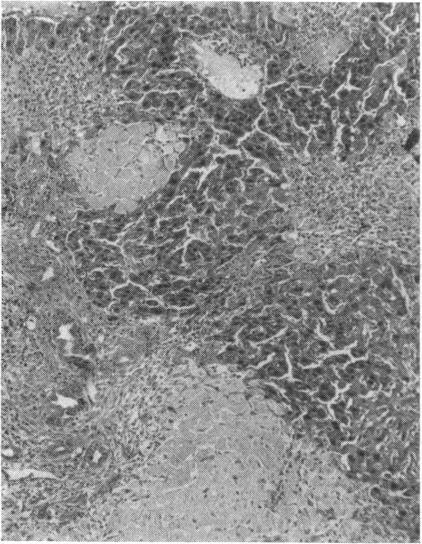

The relation between ammonia intoxication and liver disease is not clear. Ammonia appears to be relatively non-toxic to normal individuals, whereas some patients with liver disease appear to be exquisitely sensitive to dietary protein, ammonia-releasing substances, and ammonium salts. In an attempt to elucidate this relationship the intravenous LD(50) of ammonium chloride was determined in both normal mice and in those with liver disease produced by a variety of means. Parenchymal damage was created by acute and chronic carbon tetrachloride intoxication, a low-protein, lipotrope-deficient diet, and mouse hepatitis virus. Mice in which the portal vein had been partially ligated and those infected with Schistosoma mansoni developed portal-systemic collateral circulation. Groups of these mice were placed on high-protein diets and ammonia drinking water for periods as long as two months. A combination of both parenchymal damage and collateral circulation was induced in mice either by bile duct ligation or by a combination of schistosomiasis and acute carbon tetrachloride intoxication. When the above groups of mice with liver disease were compared with normal control mice in the same weight range, the LD(50) of ammonium chloride showed no striking change.

氨中毒与肝脏疾病之间的关系尚不清楚。氨对正常个体似乎相对无毒,而一些肝病患者似乎对膳食蛋白质、氨释放物质和铵盐极为敏感。为了阐明这种关系,测定了正常小鼠以及通过多种方式诱发肝病的小鼠静脉注射氯化铵的半数致死量(LD50)。通过急性和慢性四氯化碳中毒、低蛋白、缺乏促脂物质的饮食以及小鼠肝炎病毒造成实质损伤。门静脉部分结扎的小鼠以及感染曼氏血吸虫的小鼠形成了门体侧支循环。将这些小鼠分组,给予高蛋白饮食并饮用含氨的水,持续长达两个月。通过胆管结扎或血吸虫病与急性四氯化碳中毒相结合的方式,在小鼠中诱导实质损伤和侧支循环同时出现。当将上述患有肝病的小鼠组与相同体重范围的正常对照小鼠进行比较时,氯化铵的LD50没有显著变化。